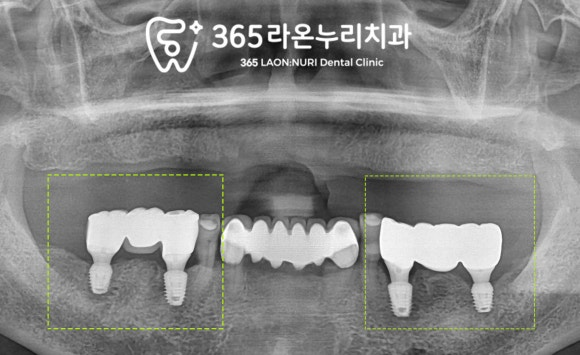

흔들리던 곳은 발치 전ct 촬영을 하여

해부학 구조와 위치를 살펴봅니다.

하치조 신경과 충분한 거리가

확보되어 있음을 확인하고

픽스처 식립 후 엑스레이를 찍고 보니

위에 틀니를 고려해 어금니 간격에 맞게

잘 심어졌네요.

식립과 동시에 뼈가 손실된 부위를

뼈이식을 통해 채워 넣었습니다.